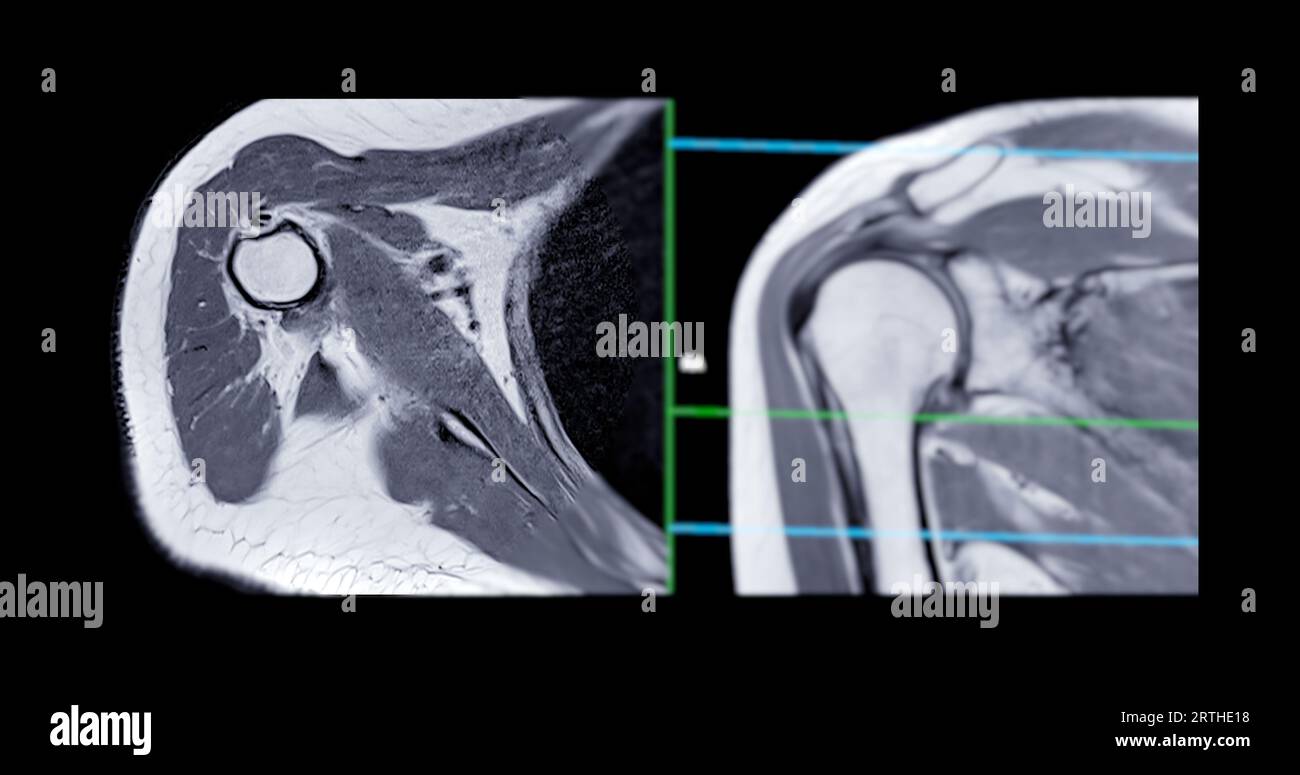

Resonance Imaging or MRI of Shoulder Joint Coronal T2 FS and PDW for diagnostic What Can Mri Of Shoulder Detect magnetic resonance imaging (mri) of the shoulder is done to: magnetic resonance imaging (mri) of the shoulder uses a powerful magnetic field, radio waves and a computer to produce. The mri allows accurate assessment of. a shoulder mri is a test that uses a magnetic field to take pictures of your shoulder. A shoulder mri can diagnose. What Can Mri Of Shoulder Detect.

MRI Shoulder Musculoskeletal Imaging